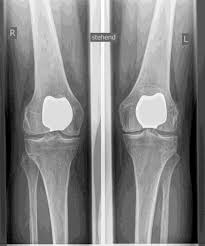

Les articulations artificielles du genou sont appelées prothèses complètes et prothèses partielles. Je vérifie soigneusement au préalable quelle prothèse vous convient sur la base de l'examen clinique, ainsi que sur la base d'images radiographiques ou IRM.

L’articulation artificielle du genou remplace la surface cartilagineuse détruite par l’arthrose. L'os sous-jacent du fémur et de la tête tibiale reste intact. Certains comparent une articulation artificielle moderne du genou à un couronnement de dent ; le terme exact est ce qu'on appelle le resurfaçage bicondylien. Entre les nouvelles surfaces sur la partie supérieure et inférieure de la jambe se trouve ce que l'on appelle une incrustation en plastique blanc spécialement durci, qui peut être vue sur l'image radiographique comme la distance entre les pièces métalliques.